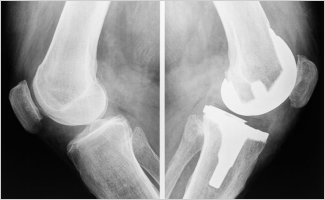

Patients who undergo total knee arthroplasty (TKA) are more likely to experience higher levels of postoperative pain based on several preoperative factors, including rates of opioid use, fatigue severity, and illness perception. This is according to a study published in the European Journal of Pain.